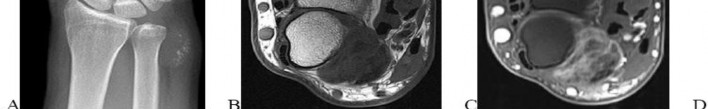

Question 2

A 45-year-old manual laborer complains of chronic radial-sided wrist pain. He recalls a severe 'sprain' 10 years ago. Radiographs demonstrate scapholunate dissociation with advanced radioscaphoid arthritis. MRI confirms the radiolunate joint is spared, but the proximal capitate shows severe, full-thickness chondral wear.

Which of the following procedures is most appropriate to provide durable pain relief while preserving motion?

Explanation

The patient has Scapholunate Advanced Collapse (SLAC) pattern of the wrist. Stage III SLAC involves the capitolunate joint, while the radiolunate joint characteristically remains spared. Because the capitate head is severely arthritic, Proximal Row Carpectomy (PRC) is contraindicated, as it relies on a healthy cartilage interface between the capitate and the lunate fossa. Scaphoid excision with four-corner fusion (capitate, hamate, lunate, triquetrum) is the procedure of choice.